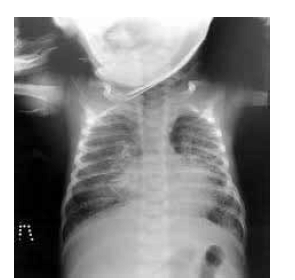

Um lactente de um mês de idade, nascido de parto vaginal, apresentava tosse seca havia uma semana. O exame físico do bebê constatou temperatura axilar de 37 ºC, hiperemia, edema e secreção serosa em conjuntivas, leve taquipneia e murmúrio vesicular rude com creptações disseminadas à ausculta pulmonar. Foi realizada radiografia do tórax, conforme ilustrado a seguir.

Nesse caso, o diagnóstico mais provável é pneumonia por Chlamydia trachomatis, e o tratamento do paciente deve ser realizado com azitromicina, na dose de 30 mg/kg por cinco dias.